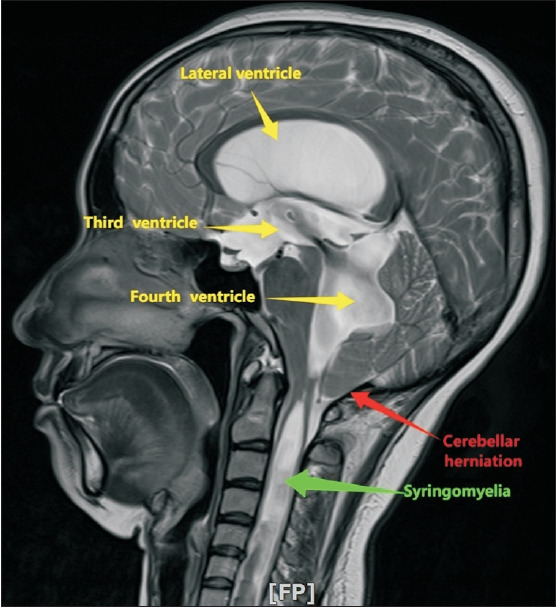

Chiari malformation type I (CMI) is a structural abnormality characterized by cerebellar tonsil herniation through the foramen magnum, often leading to disrupted cerebrospinal fluid dynamics and syringomyelia. While CMI commonly presents with occipital headaches and neck pain, atypical manifestations, such as bilateral foot drops, are exceedingly rare. We describe a 37-year-old female patient presenting with bilateral foot drop, which was later established to be caused by syringomyelia secondary to CMI. Magnetic resonance imaging revealed an 8 mm tonsillar descent and a syrinx extending to the conus medullaris. The patient refused surgical intervention and opted for conservative management; partial functional recovery was subsequently observed. This report emphasizes the importance of recognizing rare neurological presentations of CMI. To our knowledge, this is the first documented case of CMI with syringomyelia presenting as a bilateral foot drop.